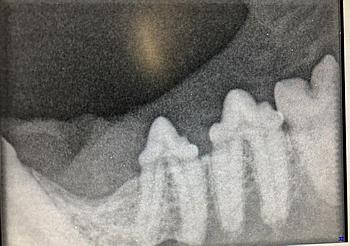

Katze: FORL beim 2 jähriger Kater